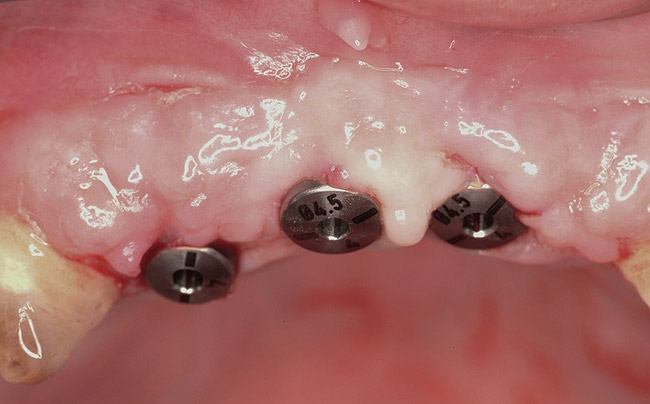

Figure 2  Tenacious soft tissue incorporates around titanium mesh, which is used for ridge augmentation and removed at time of implant placement.

Figure 2